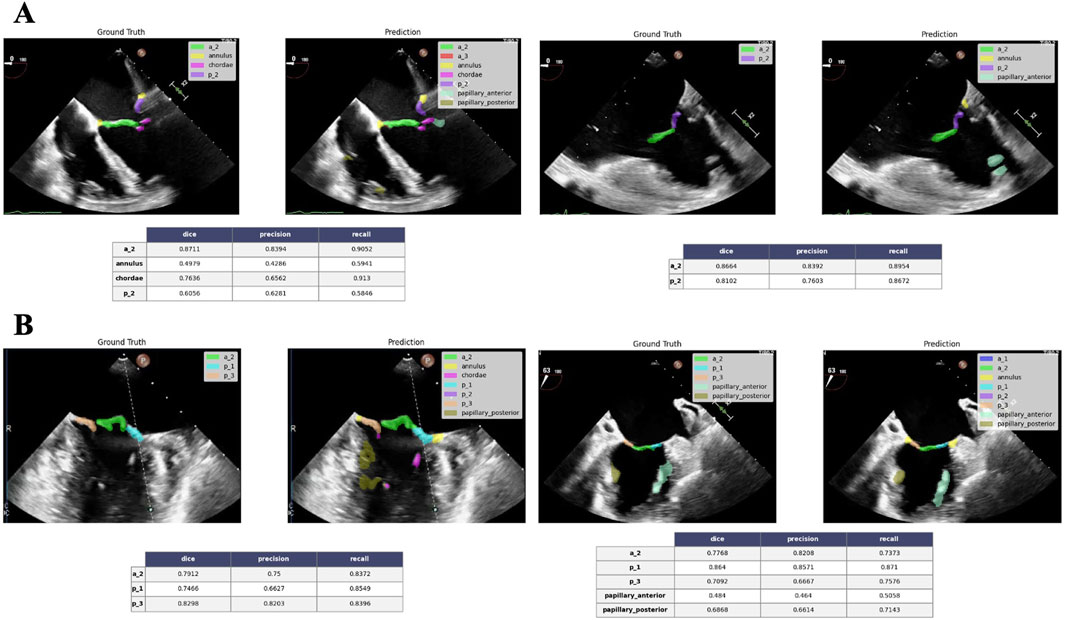

Background: Severe mitral valve regurgitation requires comprehensive evaluation for optimal treatment. Initial screening uses transthoracic echocardiography (TTE), followed by transesophageal echocardiography (TEE) to determine eligibility for adequate intervention. Mitral Transcatheter Edge-to-Edge Repair (M-TEER) indications are based on detailed and quality valve and sub-valvular apparatus assessment, including anatomy and regurgitation pathophysiology. Aim: To develop AI algorithms for standardizing M-TEER eligibility assessment using TTE and TEE echocardiograms, supporting all stages of mitral valve regurgitation evaluation to assist non-expert centers throughout the entire process, from severe mitral valve regurgitation diagnostic to M-TEER procedure. Methods: Three deep learning algorithms were developed using echocardiographic data from M-TEER patients performed at Montreal Heart Institute (2018-2025). 1) ECHO-PREP was trained to identify key diagnostic views in TTE (n=530) and diagnostic and procedural views in TEE (n=2222) examinations to determine the level of quality images needed to do a M-TEER. 2) 4D TEE segmentation with automated mitral valve area (MVA) quantification (n=221), and (3) 2D TEE scallop-level segmentation of leaflets and sub-valvular structures (n=992). Results: Preliminary results on test sets showed 95.7% accuracy in TTE view classification and 91% accuracy for TEE view classification. The 4D segmentation module demonstrated excellent agreement with manual MVA measurements (R=0.84, p<0.001), successfully discriminating patients undergoing M-TEER from those referred for surgical replacement (p=0.046 for AI predictions). The 2D scallop-level analysis achieved a mean Dice score of 0.534 across 11 anatomical structures, with better performance in commonly represented configurations (e.g., A2-P2, P1-A2-P3). Conclusion: ECHO-PREP demonstrates the feasibility of an integrated AI-assisted workflow for MR assessment, combining quality control, dynamic 4D valve quantification, and scallop-level anatomy interpretation. These results support the potential of AI to standardize M-TEER eligibility, reduce inter-observer variability, and provide decision support across centers with different levels of expertise.